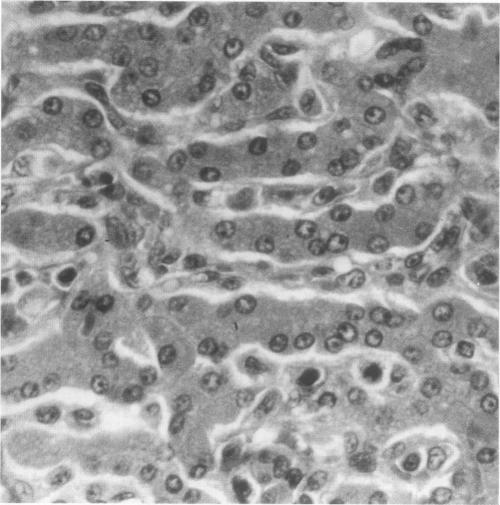

We describe the occurrence of acute monocytic leukemia in a dog with X-linked severe combined immunodeficiency (XSCID) that had been raised in a gnotobiotic environment for 20 months. This case represents the first reported instance of malignancy in canine XSCID, the first case of acute monocytic leukemia in any species with severe combined immunodeficiency, and the first documented malignancy in any species with XSCID that was not associated with immunotherapy.

我们描述了一只患有X连锁重症联合免疫缺陷(XSCID)的犬发生急性单核细胞白血病的情况,这只犬在无菌环境中饲养了20个月。该病例是犬XSCID中首次报道的恶性肿瘤实例,是任何重症联合免疫缺陷物种中的首例急性单核细胞白血病病例,也是任何XSCID物种中首例有记录的与免疫治疗无关的恶性肿瘤。